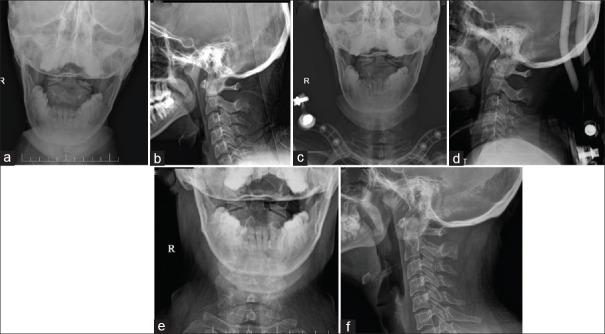

The options for the management of type II odontoid fractures in young patients include anterior screw fixation, posterior spinal fusion, or halo-vest immobilization (HVI). However, there is a recent trend away from nonoperative management and an increase in primary operative stabilization across several centers. Hence, our study aims to compare the functional and radiological outcomes of type II odontoid fractures in young patients managed with HVI and surgery.

A retrospective analysis of 70 patients with type II odontoid fracture who were managed in our institution with a mean age of 47 years was included in our study. The clinical details included the Neck Disability Index (NDI), Visual Analog Scale (VAS) for neck pain, and S-Range of Movement (ROM)-Neck score. Radiological details included union status, atlanto-dens interval, amount of displacement and angulation, and transverse ligament injury. Both the clinical and radiological parameters were compared between the patients who underwent HVI ( = 28) and surgery ( = 42).

The mean ± standard deviation follow-up duration was 4.2 ± 2.5 years in the HVI group and 3.8 ± 2.7 years in the surgery group. Of the clinical parameters, the S-ROM-Neck score was significantly better in the HVI group than in the surgery group ( < 0.001). The length of hospitalization was much shorter in the HVI group ( < 0.001). There were no differences in NDI, VAS for neck pain, and other radiological parameters.

For type II odontoid fractures in young patients, HVI had better clinical outcomes compared to the surgery and should be considered the first line of management.